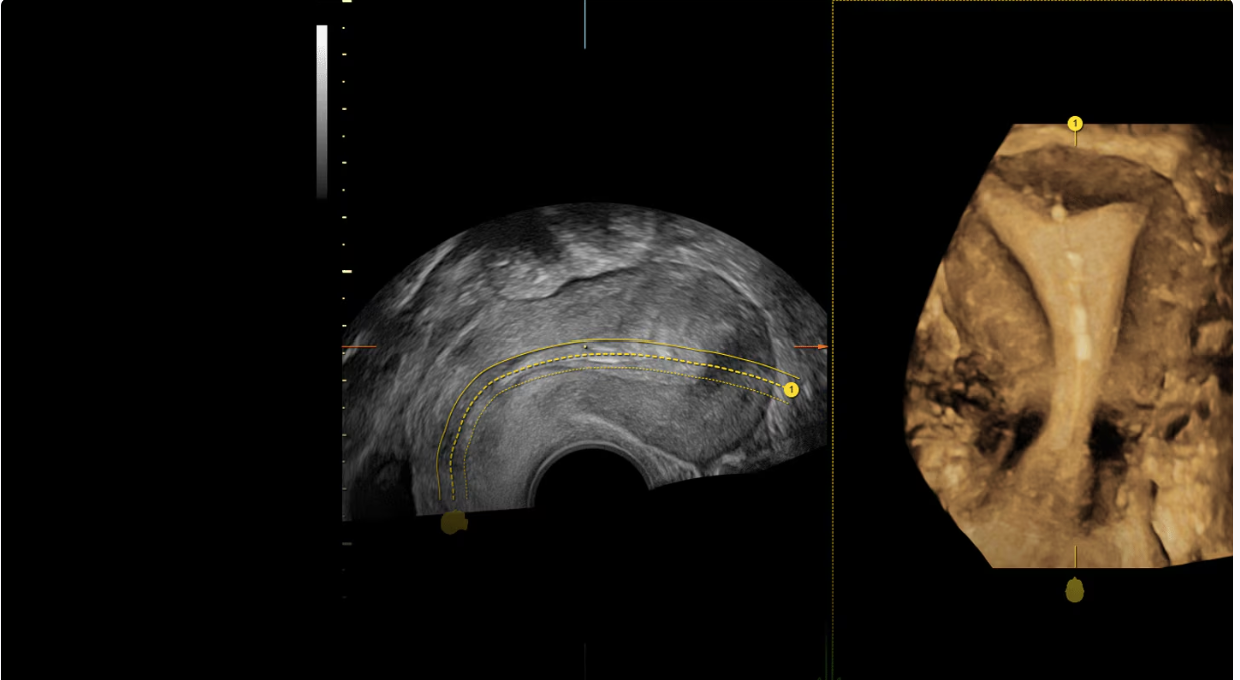

Ультразвуковой аппарат GE Voluson Expert 18 задаёт новый стандарт диагностической визуализации, особенно для сложных акушерских и гинекологических исследований. Созданная на основе усовершенствованной архитектуры Lyric, эта система повышает разрешение и чёткость изображений, обеспечивая превосходные возможности 2D/3D/4D-визуализации для уверенной и точной диагностики. Технология SonoLyst на базе искусственного интеллекта упрощает рутинные исследования, автоматически определяя анатомические особенности плода и оптимизируя измерения, что экономит время и повышает единообразие результатов.

- Инструменты автоматизации: SonoLyst, SonoPelvicFloor и SonoAVC для улучшения рабочего процесса

- Lyric Architecture: повышает разрешение изображений и вычислительную мощность для получения точных изображений с высоким разрешением.

- Технология SonoLyst: автоматизация на базе искусственного интеллекта, которая сокращает время исследования до 40%, с распознаванием анатомии плода и аннотациями измерений.

- Объемная и допплеровская визуализация: улучшает визуализацию сложных анатомических структур, способствуя точной диагностике.

Лирическая архитектура

Сложные экземы